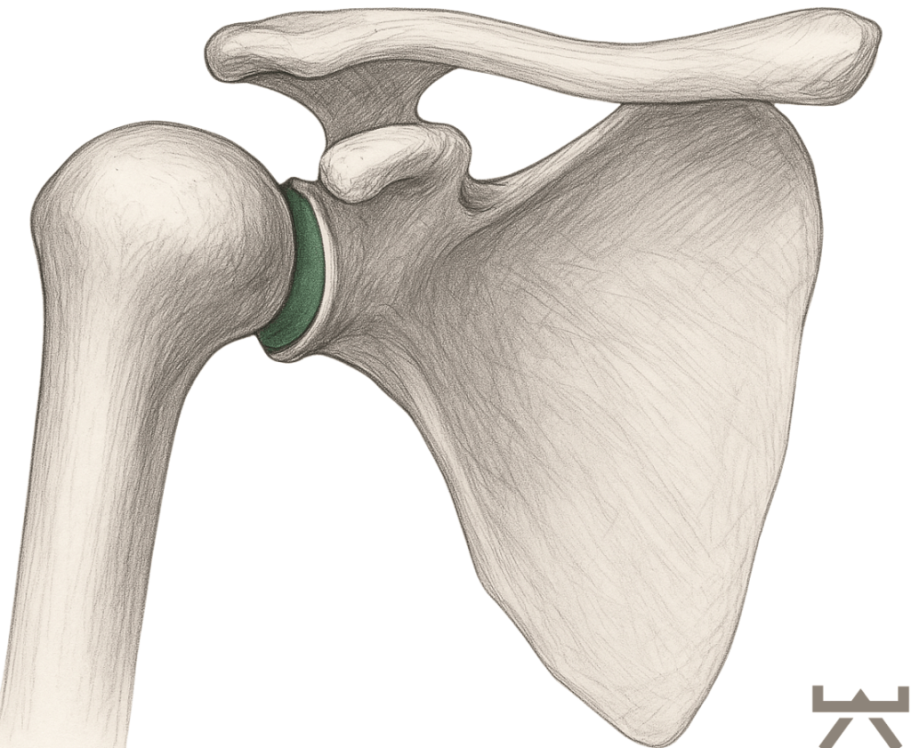

Verglichen mit der tiefen knöchernen Hüftpfanne ist die Schulterpfanne eher als kleine Schale zu bezeichnen. Diese Schale wird durch das Labrum noch verstärkt. Das Labrum ist einen Knorpelring, der direkt an der Gelenkpfanne der Schulter ansetzt. Das Labrum ist wiederum mit den Muskeln der Rotatorenmanschette verbunden, die zusammen die Schulterkapsel bilden. Sie sollten diese Muskeln als eine dynamische Gelenkpfanne betrachten, die zur Stabilisierung des Schulterkopfes beiträgt, indem sie genau im richtigen Moment angespannt wird, wenn sie ihre Bewegungen ausführen.

Für die Anforderungen, die wir an die Schulter stellen, ist ihre Anatomie sehr sinnvoll. Die minimale Gelenkpfanne ermöglicht es uns, den Arm frei in allen Richtungen zu bewegen. Durch diese Bewegungsfreiheit wird die Stabilisierung der Schulter für den Körper jedoch schwieriger.

Wie sie bei Absatz „Anatomie“ mitbekommen haben, ist die Schulter von allen Gelenken im menschlichen Körper, bei weitem das Gelenk, dass am häufigsten auskugelt. Dies ist nicht verwunderlich, wenn man die Größe der Schulterpfanne vergleicht mit dem Schulterkopf.

Da die Gelenkkongruenz (die Deckungsgleichheit oder Kontaktfläche des Gelenks) also minimal ist, muss die Stabilität des Gelenks, vor allem von unserer Muskulatur, kompensiert werden.